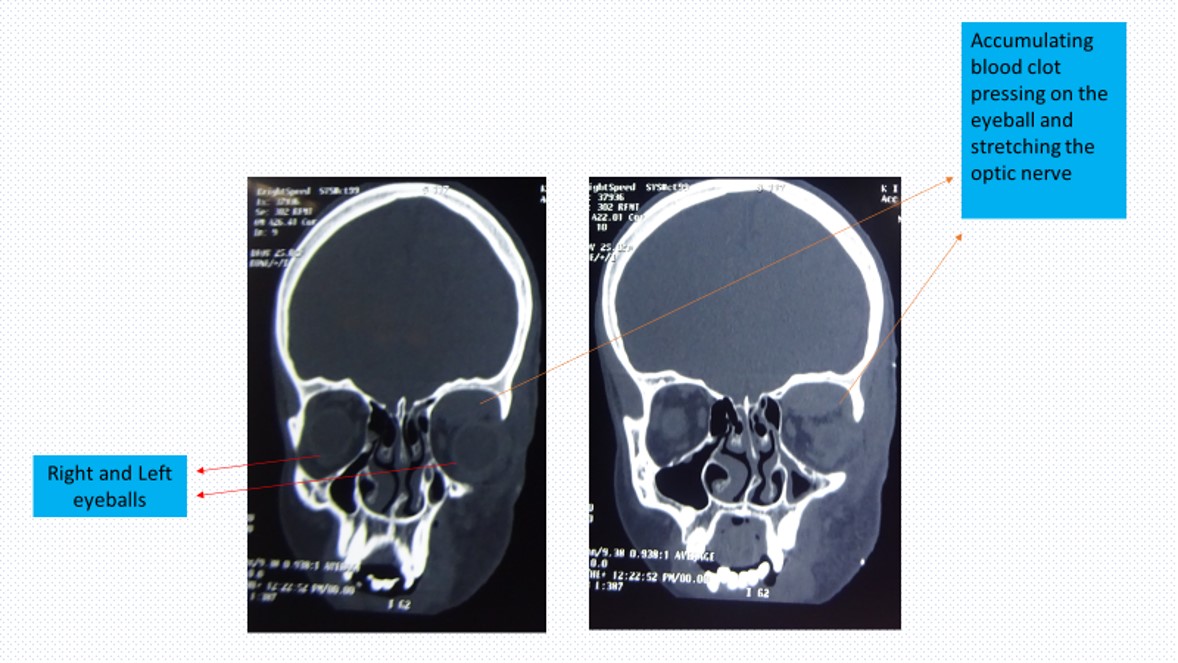

The CT scan films of the boy arrived in the evening but the radiologist hadn’t reported it yet-being a Sunday! Looking at the films the resident sent me, I noticed an intra-orbital hematoma (a blood collection within the eye socket) pressing on the nerves of the eye. I immediately asked the resident to examine the patient again for changes. She called back alarmed that the child’s eye was proptosed (protrusion of the eye) along with deterioration of the vision in that eye and it was progressing fast. I was highly annoyed with the resident for not keeping a close eye on the child even though there was nothing in the initial presentation to suggest the rather dramatic turn of events.

Back home, we were preparing to get admitted to the hospital. We were packing stuff so that we could get admitted to the hospital early. I was really in two minds as to what to do when the resident’s urgent call came. I wouldn’t have time to find another surgeon at short notice to drain the clot. If we waited any longer, the boy could lose his vision and his eye would be permanently damaged. I also wanted to be there for Priyanka, while she was experiencing a very tenacious period of our life- the birth of our first child. Both of us were worried about the latest developments as well as an early unplanned labour. When I told Priyanka about this case, I expected her to be upset and get angry at me for this situation. However, she told me to go quickly to the hospital to save the child’s vision and that we can possibly delay her admission to the hospital by a few hours. I instructed my parents who were at home to take her to the hospital if anything happens in the time I’m not there and then rushed to the hospital for the emergency surgery. As I rushed to the hospital, my very capable residents and the anaesthesia team had mobilised the child to the OT for the emergency general anaesthesia and surgical procedure. Almost in a TV-series like scenario, I ran to the OT and immediately decompressed the orbit (drained the eye socket of the blood clot) and repaired the eyelid laceration (cut). The surgery was a simple one but had to be done at the right time. The child’s eye immediately recovered on table. This below is me aspirating the blood clot- just in time